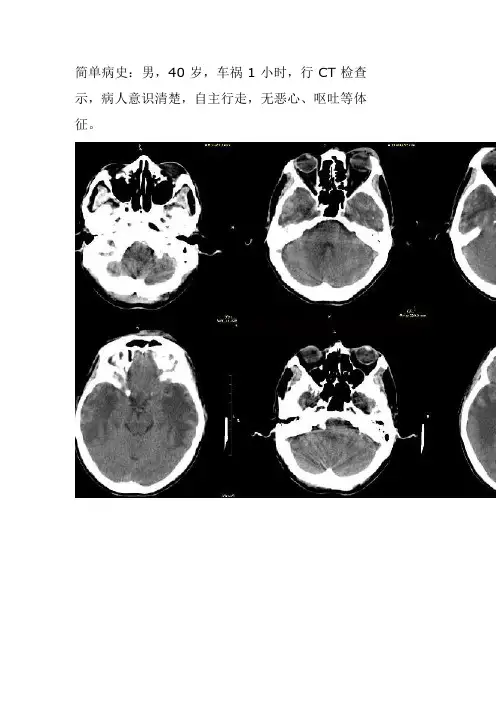

简单病史:男,40岁,车祸1小时,行CT检查示,病人意识清楚,自主行走,无恶心、呕吐等体征。

影像分析:双侧颞叶指状水肿,由颅中窝向上发展,考虑放射性脑病,一般多是鼻咽癌放疗后改变,请详细询问患者既往病史病理:鼻咽癌放疗术后鉴别:肾上腺脑白质营养不良脑转移瘤因是别人碰伤,病人及家属当时隐满病史,后仔细追问病史,患者8年前鼻咽癌放疗病史,且3年前ct和mr已诊断为放射性脑损伤。

1.mr对显示放射性脑损伤是最好的诊断方法:在t 1加权像上绝大多数呈低信号,少数呈等信号,低信号不均匀,病灶中间有更低信号区,表现组织坏死、囊变。

t2加权像上为高信号,高信号中间可以有不均匀,t2加权像是检测放疗后早期并发症的最好的检查方法之一。

放射性脑损伤的病灶以不规则的为多,其次为椭圆形及圆形,少数为长条形,病灶周围有水肿。

注射gd-dtpa后脑坏死可有强化表现,而水肿无强化。

2.CT平扫为局限性脑实质低密度改变,为脑组织的水肿、脱髓鞘和坏死所致,增强扫描多不强化,但是少部分病例可以出现不规则或环形强化。

本病以脑恶性肿瘤,特别是胶质瘤及鼻咽癌放疗后多见。

本病的发生部位与放射线治疗野相一致,如鼻咽癌的病变多在两侧颞极。

放射性脑损伤的鉴别诊断应与肿瘤复发、脑干胶质瘤、脑梗塞鉴别。